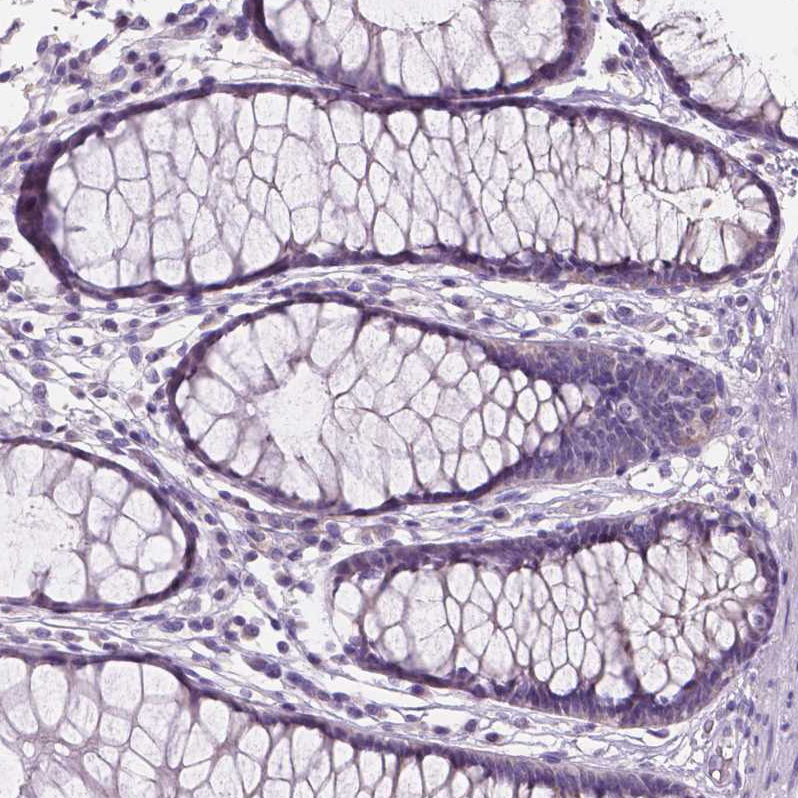

Immunohistochemistry analysis in human skin and kidney tissues using HPA062568 antibody. Corresponding SBSN RNA-seq data are presented for the same tissues.